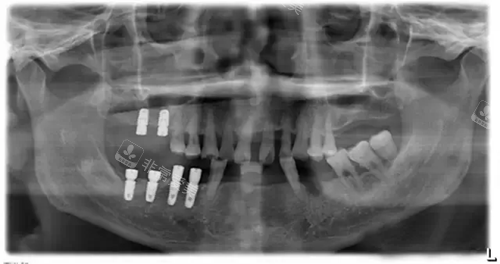

韩国奥齿泰种植体X光片.webp

韩国奥齿泰种植体型号